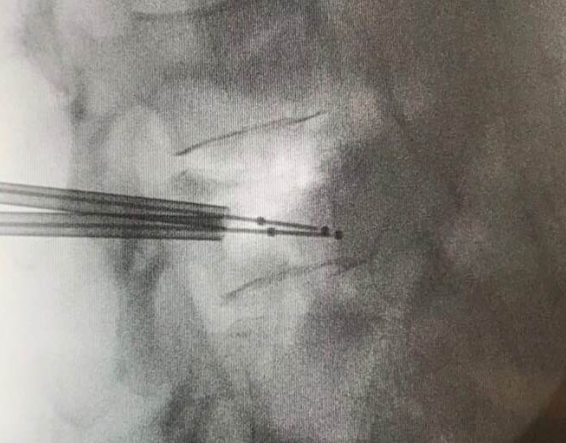

椎體成形術

椎體成形術俗稱打骨水泥,是以針孔微創的手術,把人造骨粉(丙烯酸膠粘劑)注射到脊椎椎體骨折下陷的地方,強化並鞏固因骨質疏鬆導致脆弱的骨骼,重建椎體的骨骼形狀以防止下陷前傾的骨椎進一步惡化(見圖二至五)。適合進行椎體成形術的情況包括(1)因骨折造成的持續腰背痛;(2)因嚴重骨質疏鬆致骨骼脆弱,脊骨前傾及出現駝背現象;(3)任何藥物都起不了作用。這項小手術只須一小時的時間,病人可在術後24小時回家,不須再服止痛藥,但須服用抗骨質疏鬆藥物,來預防脊椎、盤骨或其他部位骨折及下陷。

椎體成形術是以針孔微創的手術,注射人造骨粉(丙烯酸膠粘劑)到脊椎椎體

圖四

胸椎12節及腰椎第3節骨折完 成椎體成形術